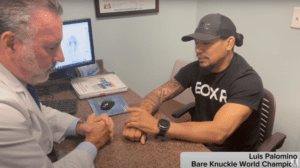

Hand Pain: Video Content

Engage with informative videos delving into the intricacies of hand discomfort, exploring its diverse causes and effective remedies. From expert interviews elucidating underlying conditions to step-by-step guides on therapeutic exercises, these videos offer valuable insights to empower you in managing and preventing hand pain.